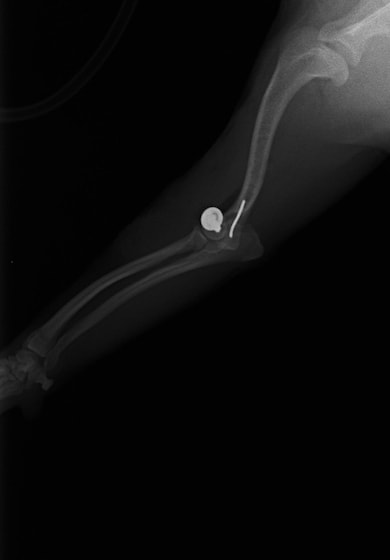

症例3:キルシュナーワイヤーのピンニングによる整復

ペルシャ猫 11ヶ月齢 雄

他院にて左大腿骨遠位の成長板骨折(salter-harrisⅠ型)が認められており、治療相談を目的として来院。当院にて、キルシュナーワイヤーを用いたピンニングにより骨折部位の整復を行いました。術後の経過は良好で、現在も経過観察中です。

術前レントゲン

術後レントゲン